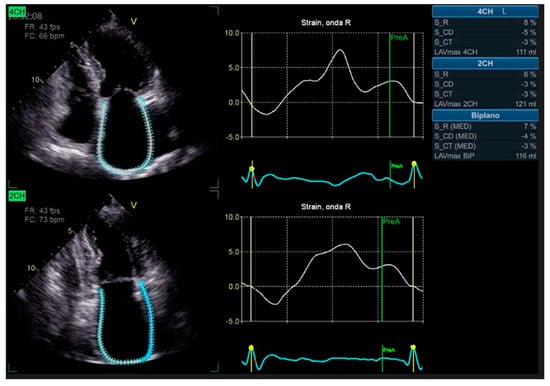

Advanced strain echocardiography can be employed to evaluate atrial function in HT recipients. Bech-Hanssen et al. [19] highlighted a significant reduction in atrial reservoir function among HT recipients, evaluated using speckle tracking. This reduction was attributed to elevated PCWP, enlargement of the LA, and impaired longitudinal RV function. The decline in atrial reservoir function is most noticeable when there are elevated filling pressures. Zhu et al. [20] observed alterations in LA function throughout all phases of the cardiac cycle, independent of the surgical technique employed. Peak LA strain was found to be associated with worse LV systolic function, suggesting the potential importance of LA function in HT patients. LA strain measurements are generated from six atrial segments, acquired from both the apical four-chamber and two-chamber views, as shown in Figure 1.

Figure 1. Two-dimensional left atrial strain using speckle tracking echocardiography obtained from the apical four-chamber (upper panel) and two-chamber (lower panel) views.